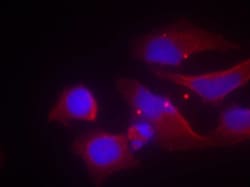

Western Blot, Immunocytochemistry

A suggested positive control for Western blot is A431 cells; suggested positive control for ICC/IF is Hela cells.